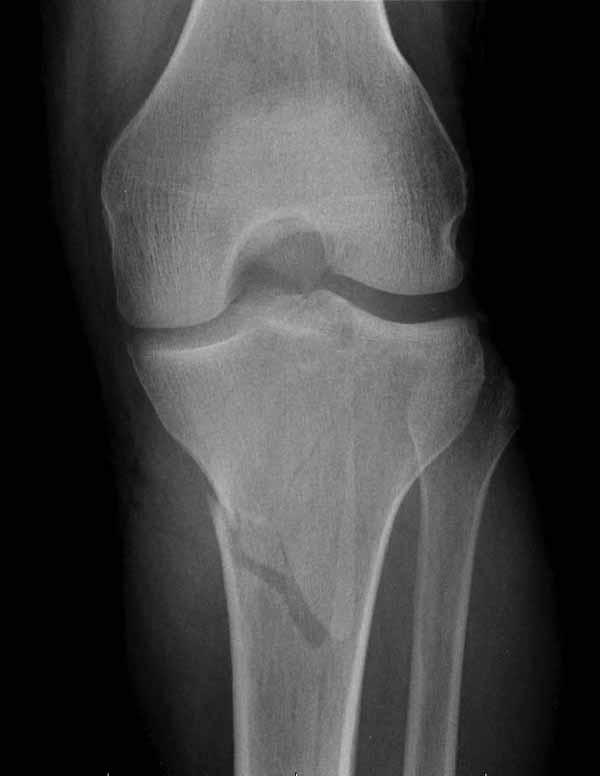

Двухколоннный перелом тибиал плато с вовлечением проксимального диафиза. Внутрисуставной компонент без смещения, и такой перелом можно лечить любым из описанных методов, о которых говорят наши коллеги.

Удобно аппаратом Илизарова или интрамедуллярным гвоздем. Гвозди не так сложно, как пугают, тем более Александр готов помощь с методичкой. Сперва надо установить компрессирующие шурупы на мыщелки. Давно отказались в пользу 3.5-4.0 мм кортикальных вместо толстых спонгиозных, потому что не доказаны преимущества толстых шурупов. Тонкие шурупы в субхондральной зоне смотрятся намного элегантнее, чем толстые 6.5.

Это мероприятие превращает перелом в простой диафизарный, который легко можно фиксировать гвоздем. Шурупы надо установить сзади предполагаемого места введения гвоздя.

Частая ошибка, когда фиксацию двух колонного перелома проводят одиночной пластиной, т.е с одной стороны, и такая фиксация не удерживает, происходит вторичноое смещение. Необходимо нейтрализовать второй пластиной или дополнительным наружным фиксатором.

Кстати, коллеги правы для уточнения характера перелома надо делать Компьютерную Томографию.